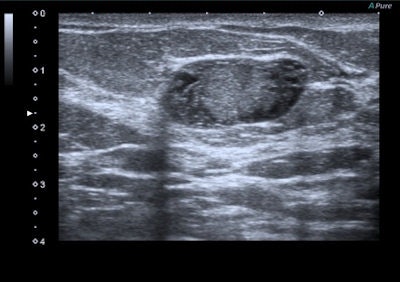

A 45-year-old woman with a palpable mass in the lower-outer quadrant 2 cm away from the nipple. There was no erythema, ecchymosis, skin ulceration, or dimpling and no axillary lymphadenopathy was detected. Baseline ultrasound shows an isoechoic lump with regular margins, with some cystic areas within. At elastography the nodule presents a color map score 4 according to the Ueno-Itoh classification, with absence of elasticity, depicted as a completely blue area with a different peripheral glow. Placing two different regions of interest (in normal breast tissue and within the nodule), strain ratio obtained is 8.96. Gross pathology confirmed a cystic cancer.

Benign lesions are described at elastography as lesions with a low color map score (score 1-2), while the best cut-off point for discriminating benign from malignant masses falling at the 3-4 boundary of color map classification, according to the Ueno-Itoh score system. Cysts often appear as hard and low deformable lesions, commonly represented with a blue pattern at the color map and with a high strain ratio because of their low compressibility.

Malignant lesions usually present with features such as acoustic shadow, spicules, indented margins, hyperechogenic halo with desmoplastic reaction around the lesion, calcifications, spreading along the ducts, and significant vascularization. Cancer can also have nonspecific features such as uneven architecture and gland edema.

Tumor stiffness is a characteristic of extracellular matrix, modulated by collagen cross-linking. Malignant lesions are less prone to deformation by pressure than normal breast tissue and have a more complex elastic modulus. Softer malignant lesions, including medullary, mucinous, papillary, cystic, and some necrotic infiltrating ductal carcinomas, are uncommon.

Elastography is often used in "uncertain" lesions classified as BI-RADS 3 and 4, but it does not change medical protocol in cases of BI-RADS 1, 2, and 5 lesions. The mean elasticity score of color map was significantly higher for malignant lesions than for benign lesions (p < 0.001), usually mainly represented as blue areas in the color map.